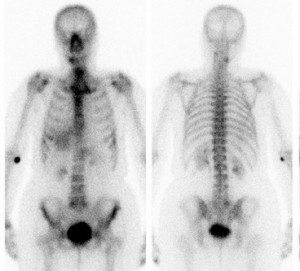

goruntu-spect-scanEnfeksiyon görüntülemede nükleer tıp yöntemleri: kemik sintigrafisi, Ga-67 sintigrafisi, nonspesifik immunoglobulinler, işaretli lökosit sintigrafisi, yeni yöntemler (işaretli antikorlar, sitokinler, işaretli antibiyotikler, PET).

Kemik sintigrafisi: Enfeksiyona spesifik değildir. Ancak enfeksiyon ayırıcı tanısında yararlıdır. Özellikle diabetik ayaklarda osteomyelit aramasında kullanılır. Ucuz ve kolay uygulanabilirliği nedeniyle tercih edilir. 3 fazlı kemik sintigrafisi: 1.kanlanma; ilk 1 dakikalık görüntüler. 2. Kan havuzu; 1 dakikalık dinamik görüntüleme sonrasındaki ilk 5 dakikalık statik görüntü. 3.Geç statik; 2-4 saat sonraki statik görüntüleme. 4.faz; 24. saatte alınan görüntü.

kemik-sintigrafiNonspesifik immunoglobulinler: Lokal permiabilite artığına bağlı olarak infeksiyon ve inflamasyon bölgesinde birikir. Indium 111 veya Tc-99m ile işaretlenirler. Kronik infeksiyonların tanısında Indium ile işarteli (HIG) sintigrafisinin sensitivitesi daha iyidir. Akciğer infeksiyonlarında Indium-111 tercih edilir. Ektremitede yerleşimli kas iskelet infeksiyonlarının tanısı ve romatoid artritin aktivasyonunun gösterilmesinde Tc-99 m HIG tercih edilir. İşaretli lökosit sintigrafisinin yapılamadığı durumlarda alternatif bir yöntemdir.